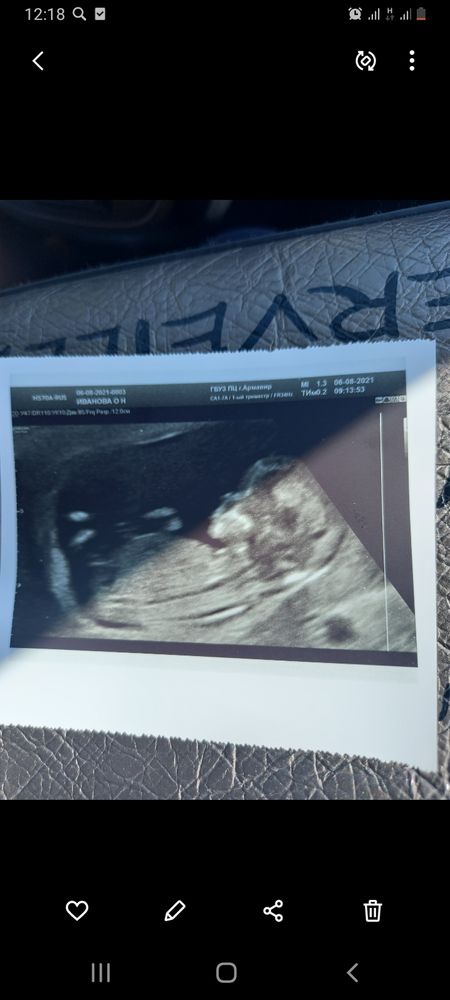

Пол малышаНа скрининге в 12 недель врач сказал"предположительно мальчик", как думаете верно? Хотелось бы конечно, больше на Узи не была

Natalie, если на вашем снимке то что я вижу - это половой бугорок, то это девочка 🤷🏼♀️

Похоже на девочку

У нас на первом скрининге такой же половой бугорок был

Я за девочку, если верно все вижу. Исправляюсь, за мальчика,я приблизила и увидела))